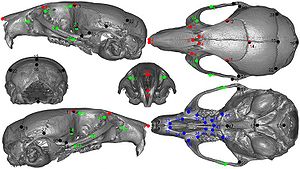

Performance of Single And Multi-Atlas Based Automated Landmarking Methods Compared to Expert Annotations in Volumetric Microct Datasets of Mouse Mandibles

Publication: Front Zool. 2015 Dec 1;12:33. PMID: 26628903 | PDF Authors: Young R, Maga AM. Institution: Center for Developmental Biology and Regenerative Medicine, Seattle Children's Research Institute, Seattle, WA, USA. Background/Purpose: Here we present an application of advanced registration and atlas building framework DRAMMS to the automated annotation of mouse mandibles through a series of tests using single and multi-atlas segmentation paradigms and compare the outcomes to the current gold standard, manual annotation. Results: Our results showed multi-atlas annotation procedure yields landmark precisions within the human observer error range. The mean shape estimates from gold standard and multi-atlas annotation procedure were statistically indistinguishable for both Euclidean Distance Matrix Analysis (mean form matrix) and Generalized Procrustes Analysis (Goodall F-test). Further research needs to be done to validate the consistency of variance-covariance matrix estimates from both methods with larger sample sizes. Conclusion: Multi-atlas annotation procedure shows promise as a framework to facilitate truly high-throughput phenomic analyses by channeling investigators efforts to annotate only a small portion of their datasets. Funding:

|

Visualization of the distances between the atlas surface that was landmarked (p90) and four other surfaces constructed. a 50 % Probability surface (p50); b 70 % Probability surface (p70); c Surface thresholded at grayscale value of 35. d Surface thresholded at grayscale value of 55. RMS: Root mean square error. Segmented left hemi-mandibles were imported into 3D Slicer and visualized using a fixed rendering and threshold setting. |